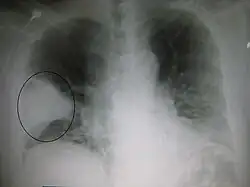

Nodule

A lung nodule is a discrete opacity in the lung which may be caused by:

- Neoplasm: benign or malignant

- Granuloma: tuberculosis

- Infection: round pneumonia

- Vascular: infarct, varix, granulomatosis with polyangiitis, rheumatoid arthritis

There are a number of features that are helpful in suggesting the diagnosis:

- rate of growth

- Doubling time of less than one month: sarcoma/infection/infarction/vascular

- Doubling time of six to 18 months: benign tumor/malignant granuloma

- Doubling time of more than 24 months: benign nodule neoplasm

- calcification

- margin

- smooth

- lobulated

- presence of a corona radiata

- shape

- site

If the nodules are multiple, the differential is then smaller:

- infection: tuberculosis, fungal infection, septic emboli

- neoplasm: e.g., metastases, lymphoma, hamartoma

- sarcoidosis

- alveolitis

- auto-immune disease: e.g., granulomatosis with polyangiitis, rheumatoid arthritis

- inhalation (e.g., pneumoconiosis)